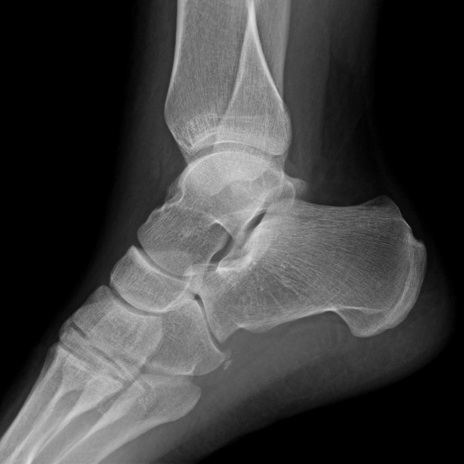

Lower Extremity